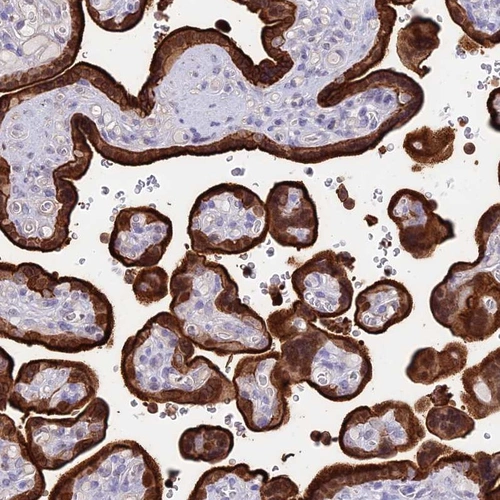

Immunohistochemical staining of human placenta shows strong cytoplasmic and membranous positivity in trophoblastic cells.